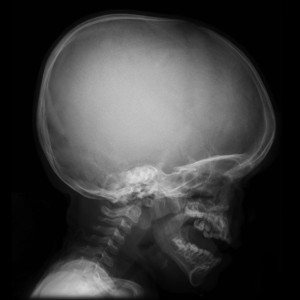

"Las craneofacias en la acondroplasia son típicas y se producen por una disminución en el crecimiento del hueso endocondral en la base del cráneo. Curiosamente, Cohen et al., han demostrado que no todos los huesos y cartílagos en la base del cráneo están involucrados de la misma manera.

Case courtesy of Dr Frank Gaillard, Radiopaedia.org. From the case Achondroplasia

Caso cortesía del Dr Frank Gaillard, Radiopaedia.org. Del caso Achondroplasia

Estas dos imágenes son usadas para comparar los tamaños de la mandíbula, del maxilar y de la base del cráneo en niños con edades similares, la primera imagen muestra a un niño sano, en la segunda el niño tiene acondroplasia.